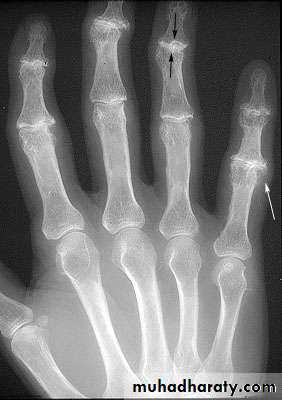

OA – Radiographic findings1. Joint space narrowing

2. Osteophyte formation (white arrow)3. Subchondral sclerosis (black arrows)

Another example of OA

Oblique and AP views

1st carpal metacarpal shows decreased joint space and subchondral sclerosis

2nd and 3rd DIP shows osteophytes and subchondral sclerosis (Heberden’s nodes)